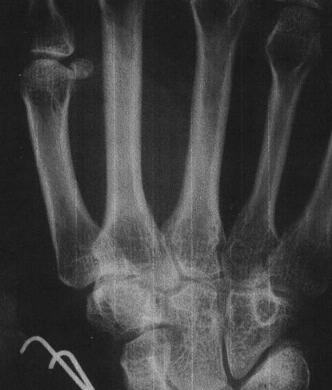

The bump on the thumb is an implant and the two things that look like "J" are pins from when my wrist was set. I think there are receptor sites in the palm of my hand which would hold drugs that could be slowly released. My hand was injected during my sleep a few days before I was kidnapped.

Xray

The x-ray was taken when I broke my wrist the "j" shape is not an implant. My wrist had to be pinned together. The implant is in the thumb and other implants may be in the palm. My hands use to glow in the dark. As I told you K's used to glow, even in the daylight!